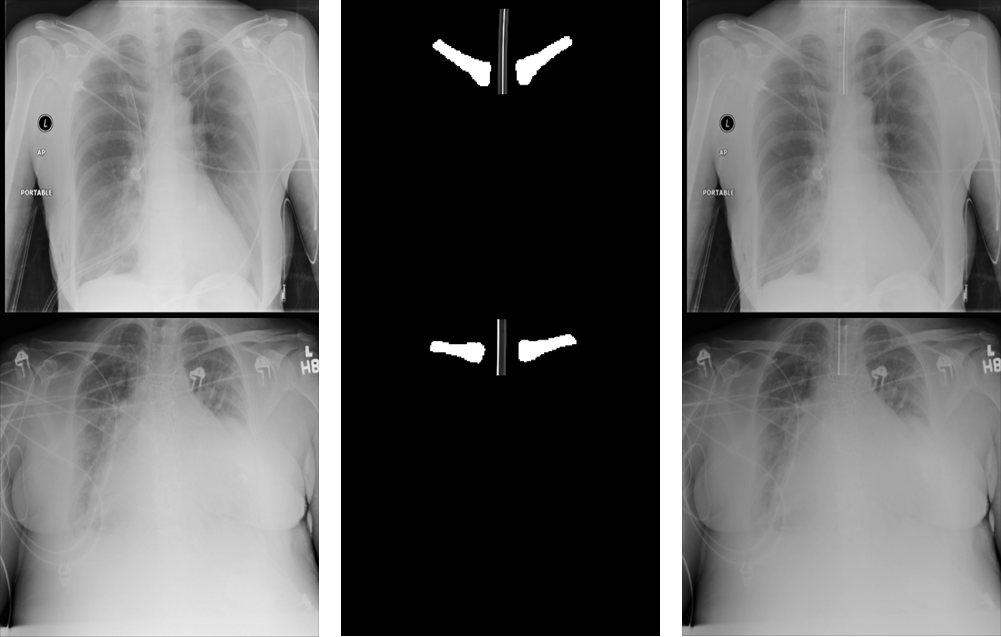

Refer to caption

Figure 2: Original X-ray images (left column), Clavicles segmentation and synthesized ET tube (middle column) and Synthesized ET tubes blended into the original X-ray (right column)

Generating the synthetic ET tubes over real X-ray images includes the following main steps as shown in Fig. 2: a) Selection of cases from the NIH dataset that do not contain ET tubes but may include other tubes (such as nasogastric (NG) tube, drainage tubes, catheters); b) Segmentation of the clavicles in order to localize the synthetic ET tube in the trachea area; c) Blending of generated synthetic ET tubes onto real X-ray images.

The last step for creating a realistic X-ray with an ET tube is to merge the synthetic tube with the real X-ray image. We selected AP X-ray images from the NIH dataset that do not contain ET tubes and blended the random synthetic ET tubes into the images. We used a simple blending with random weights in the range of [0.1,0.2]0.10.2[0.1,0.2].